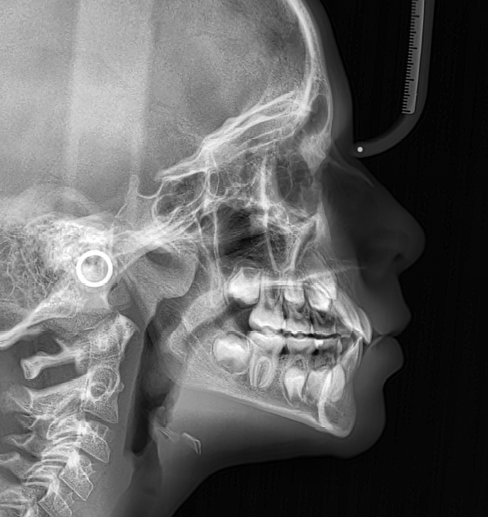

The patient presented with a skeletal Class I relationship and a mesofacial growth pattern, indicating balanced sagittal and vertical skeletal proportions. Dental examination revealed a Class I molar and canine relationship bilaterally. The patient was in the mixed dentition phase. Significant dental crowding was observed in both arches, consistent with a dentoalveolar discrepancy. Midline deviations were present, affecting dental symmetry and occlusal harmony. The maxillary lateral incisors were in crossbite, contributing to anterior transverse discrepancy and functional imbalance.

Periodontal evaluation revealed early signs of periodontal disease, primarily affecting tooth 41. Radiographic assessment demonstrated root convergence of teeth 11 and 21, indicating compromised root parallelism. Overall, the initial presentation was characterized by dentoalveolar crowding, transverse discrepancies, occlusal asymmetries, and early periodontal involvement within an otherwise favorable skeletal framework, requiring a carefully planned orthodontic approach to ensure functional stability and periodontal preservation.